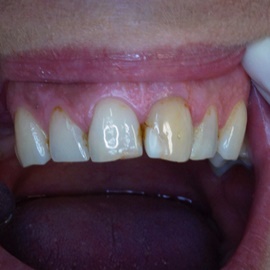

Wybielanie obejmujące pojedyncze zęby jest dość często spotykane. Najczęstszą przyczyną dyskoloracji zęba jest obumarcie miazgi i brak następowego poprawnego leczenia kanałowego, lub leczenie nieprawidłowe. Czasami udaje się przeprowadzić proces wybielania, który jest zadowalający dla pacjenta, a czasami w oparciu o uzyskany wynik można przeprowadzić leczenie protetyczne np. koroną lub licówką całoceramiczną.

Trzeba jednak uważać, ponieważ nieumiejętnie przeprowadzone wybielanie może być przyczyną resorpcji wewnętrznej i może sie skończyć utratą całego zęba...juz wybielonego. Poniżej zdjęcia przed i po leczeniu mikrochirurgicznym resorpcji.